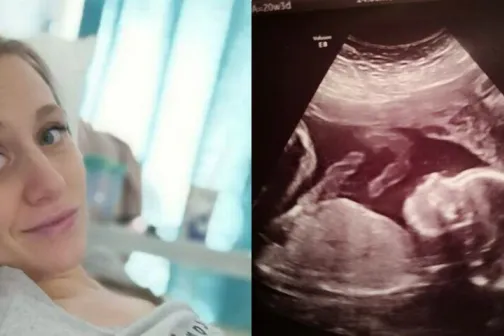

12/02/2019 -20:59

Sănătate

Premieră la Londra. Un bebeluș a fost scos din uter, operat și pus la loc